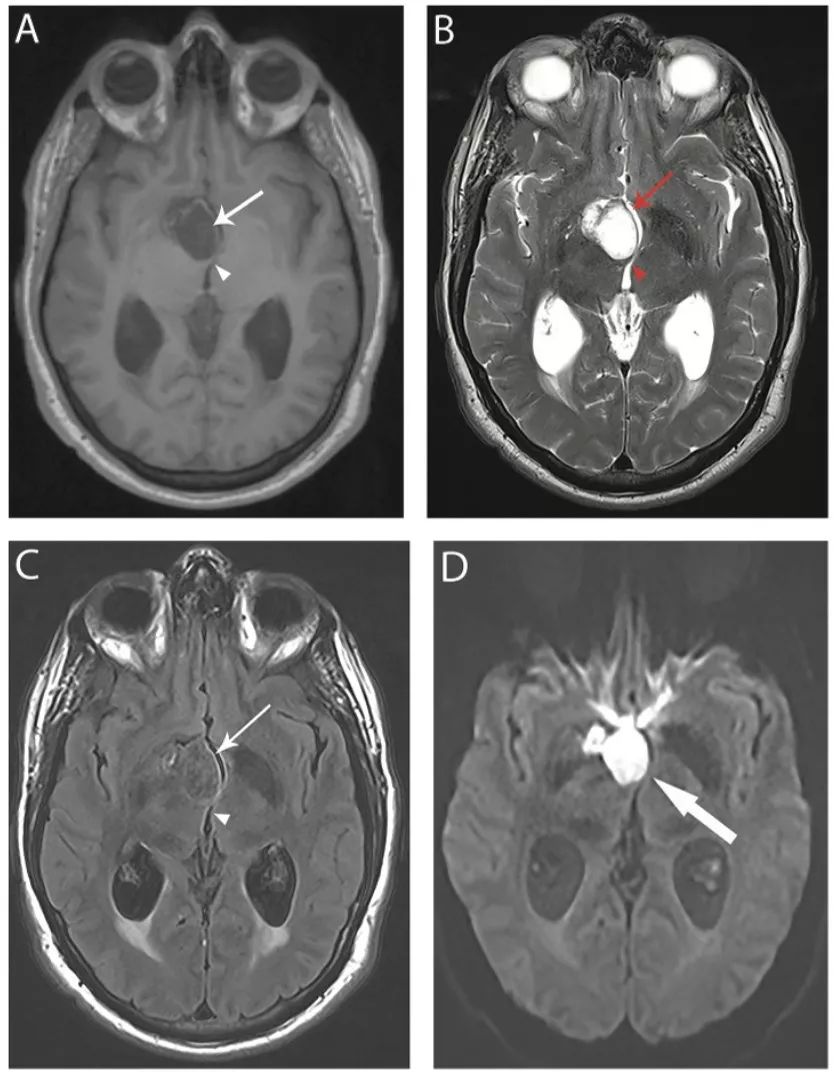

图19 表皮样囊肿

轴位T1 (A)、T2 (B)和FLAIR(C)像显示鞍上区有一个突出的囊肿(箭头),为T1低信号、T2高信号、FLAIR等信号,囊肿引起丘脑的占位效应,引起第三脑室变形(箭头)。DWI像(D)显示囊肿明显高信号(箭头),不同于蛛网膜囊肿。

图20 脑囊虫病

轴位FLAIR(A)、增强T1IW像 (B)和冠状位增强T1WI(C)显示不同时期脑囊虫病的多发囊性病灶。囊泡期可见左额叶前部薄壁囊肿,囊内物质在FLAIR为低信号,无明显增强(楔形箭头);背外侧左额叶囊肿FLAIR高信号、增强后高信号(细箭头),为胶囊囊泡或神经囊尾蚴的颗粒状结节阶段。(C)上矢状窦相邻的两个囊肿(粗箭头)。